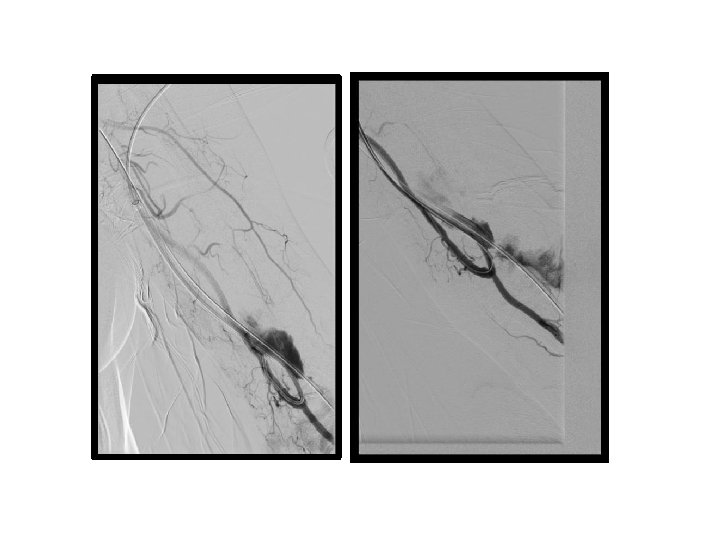

PTA sırasında oluşan venöz komplikasyonlar

• venöz rüptür (%2, 1 - 20) • akut / gecikmiş rüptür • minimal ekstravazasyon ve küçük hematom → damar duvar bütünlüğünde belirgin bozulma ve masif hematom • venöz diseksiyon

venöz rüptür • • • Manuel kompresyon Balon tamponat Stent yerleştirme Embolizasyon Cerrahi ligasyon

venöz rüptür